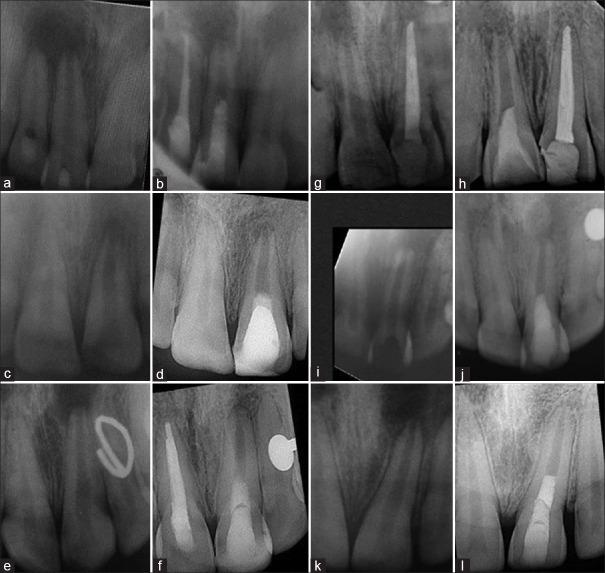

The purpose of this prospective case series was to report the long-term clinical and radiographic outcomes of regenerative endodontic procedures (REP) using platelet-rich fibrin (PRF), in traumatized immature permanent teeth with necrotic pulps. Six immature necrotic permanent maxillary central incisors from six patients were treated with REP supplemented with PRF. Patients were recalled at 6, 12, 18, 24, 36, 48, and 60 months. Radiographic changes in the radiographic root area (RRA), apical diameter, root thickness, and root length were quantified. Clinically, tooth survival in terms of tooth retention in the arch and absence of any sign and symptoms of endodontic pathology were noted. All the teeth survived and met the clinical criteria for success throughout the follow-up period. Follow-up radiographs at 5 years revealed complete resolution of the periapical lesions in all patients and the average apical diameter decrease was 30.96%. An average increase of 13.18% for root length, 40.20% for root thickness, and 26.35% for RRA were noted.

本前瞻性病例系列的目的是报告在牙髓坏死的外伤年轻恒牙中使用富血小板纤维蛋白(PRF)进行再生性牙髓治疗(REP)的长期临床和影像学结果。对6例患者的6颗上颌未成熟坏死恒中切牙进行了补充PRF的REP治疗。在6、12、18、24、36、48和60个月时对患者进行回访。对影像学根区(RRA)、根尖直径、牙根厚度和牙根长度的影像学变化进行量化。临床上,记录牙齿在牙弓中的保留情况以及有无牙髓病变的任何体征和症状方面的牙齿留存情况。所有牙齿均存活,并且在整个随访期间均符合成功的临床标准。5年的随访X光片显示,所有患者的根尖周病变均完全消退,根尖直径平均减小30.96%。观察到牙根长度平均增加13.18%,牙根厚度平均增加40.20%,RRA平均增加26.35%。